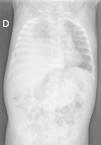

Se solicitan radiografía de tórax (fig. 1), que muestra derrame pleural con desplazamiento mediastínico, y analítica sanguínea, con hiperbilirrubinemia directa e hipertransaminasemia.